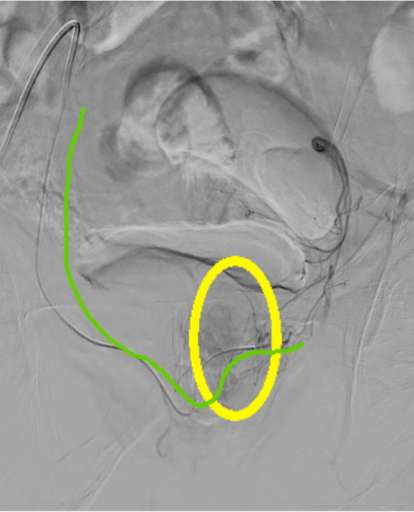

להלן תמונות נבחרות מתוך הצנתור.

הזרקת חומר ניגוד בעורק הכסל הפנימי הימני.

אפשר לראות את המעקף (מסומן בצבע אדום) המוביל דם לערמונית מימין ובהמשכו באמצעות מעקף לעורק הערמונית השמאלי (מסומן בסגול). גבולות הערמונית מסומנות בצהוב. מיקרוקטטר בירוק.